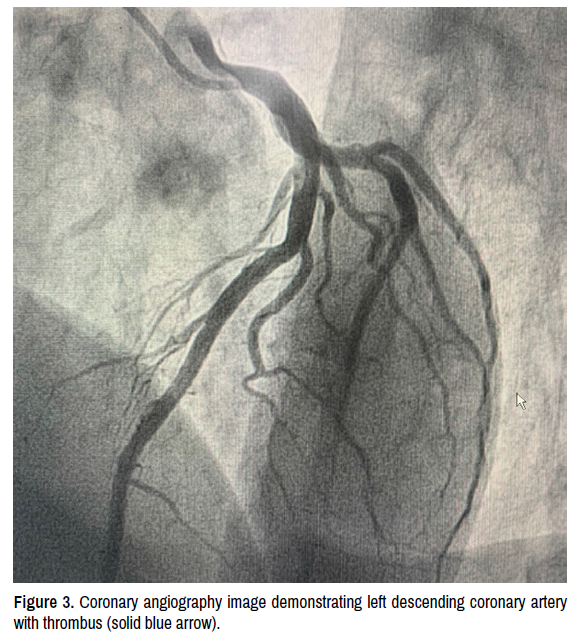

The cardiac magnet resonance revealed the presence two infarcts: mid-ventricular anterior wall and basal inferior wall (Figure 1). Further diagnostics with cardiac magnet resonance, the cardiac catheterization was arranged and showed: thrombotic content in the right coronary artery and left anterior descending arteries, with no impaired blood flow (Figures 2 and 3). We prescribed dual anti-platelet therapy and an angiotensin-convertingenzyme inhibitor. After two negative COVID-19 swab results in over 24 h and absence of typical symptoms, the patient was no longer considered infectious and could be assigned to a cardiac rehabilitation program.

clinical-case-reports-coronary-angiography

Figure 3. Coronary angiography image demonstrating left descending coronary artery with thrombus (solid blue arrow).